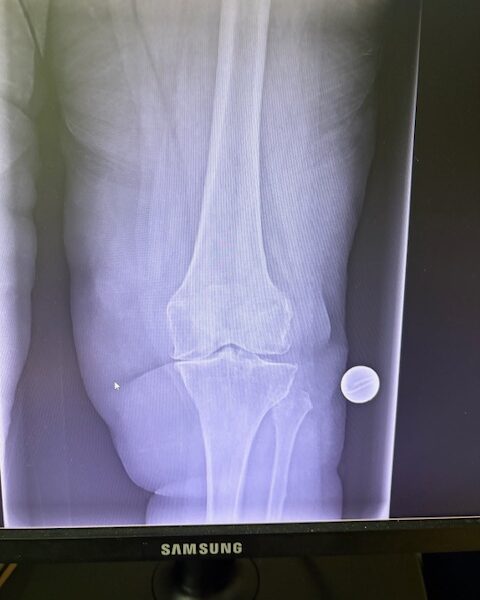

Η 80χρονη ασθενής παρουσίαζε έντονο πόνο και δυσκαμψία στο αριστερό γόνατο τα τελευταία χρόνια. Ο πόνος είχε επιδεινωθεί, επηρεάζοντας τη βάδιση και τη συνολική κινητικότητα, ενώ δυσκολευόταν ακόμα και σε απλές δραστηριότητες όπως το ανέβασμα σκαλοπατιών ή το περπάτημα σε μικρές αποστάσεις. Με την υπάρχουσα πρόθεση ισχίου στην αριστερή πλευρά η ασθενής ήταν αρκετά ευχαριστημένη. Ο ακτινολογικός και κλινικός έλεγχος ανέδειξε προχωρημένη οστεοαρθρίτιδα του αριστερού γόνατος, με πλήρη απώλεια του αρθρικού χόνδρου και παραμόρφωση του μηροκνημιαίου άξονα. Μετά από ανάλυση όλων των επιλογών, αποφασίστηκε η Ολική Αρθροπλαστική Γόνατος με Ρομποτική Υποβοήθηση, με στόχο την απόλυτη ακρίβεια στην τοποθέτηση των εμφυτευμάτων και την αποκατάσταση της φυσιολογικής μηχανικής του γόνατος.